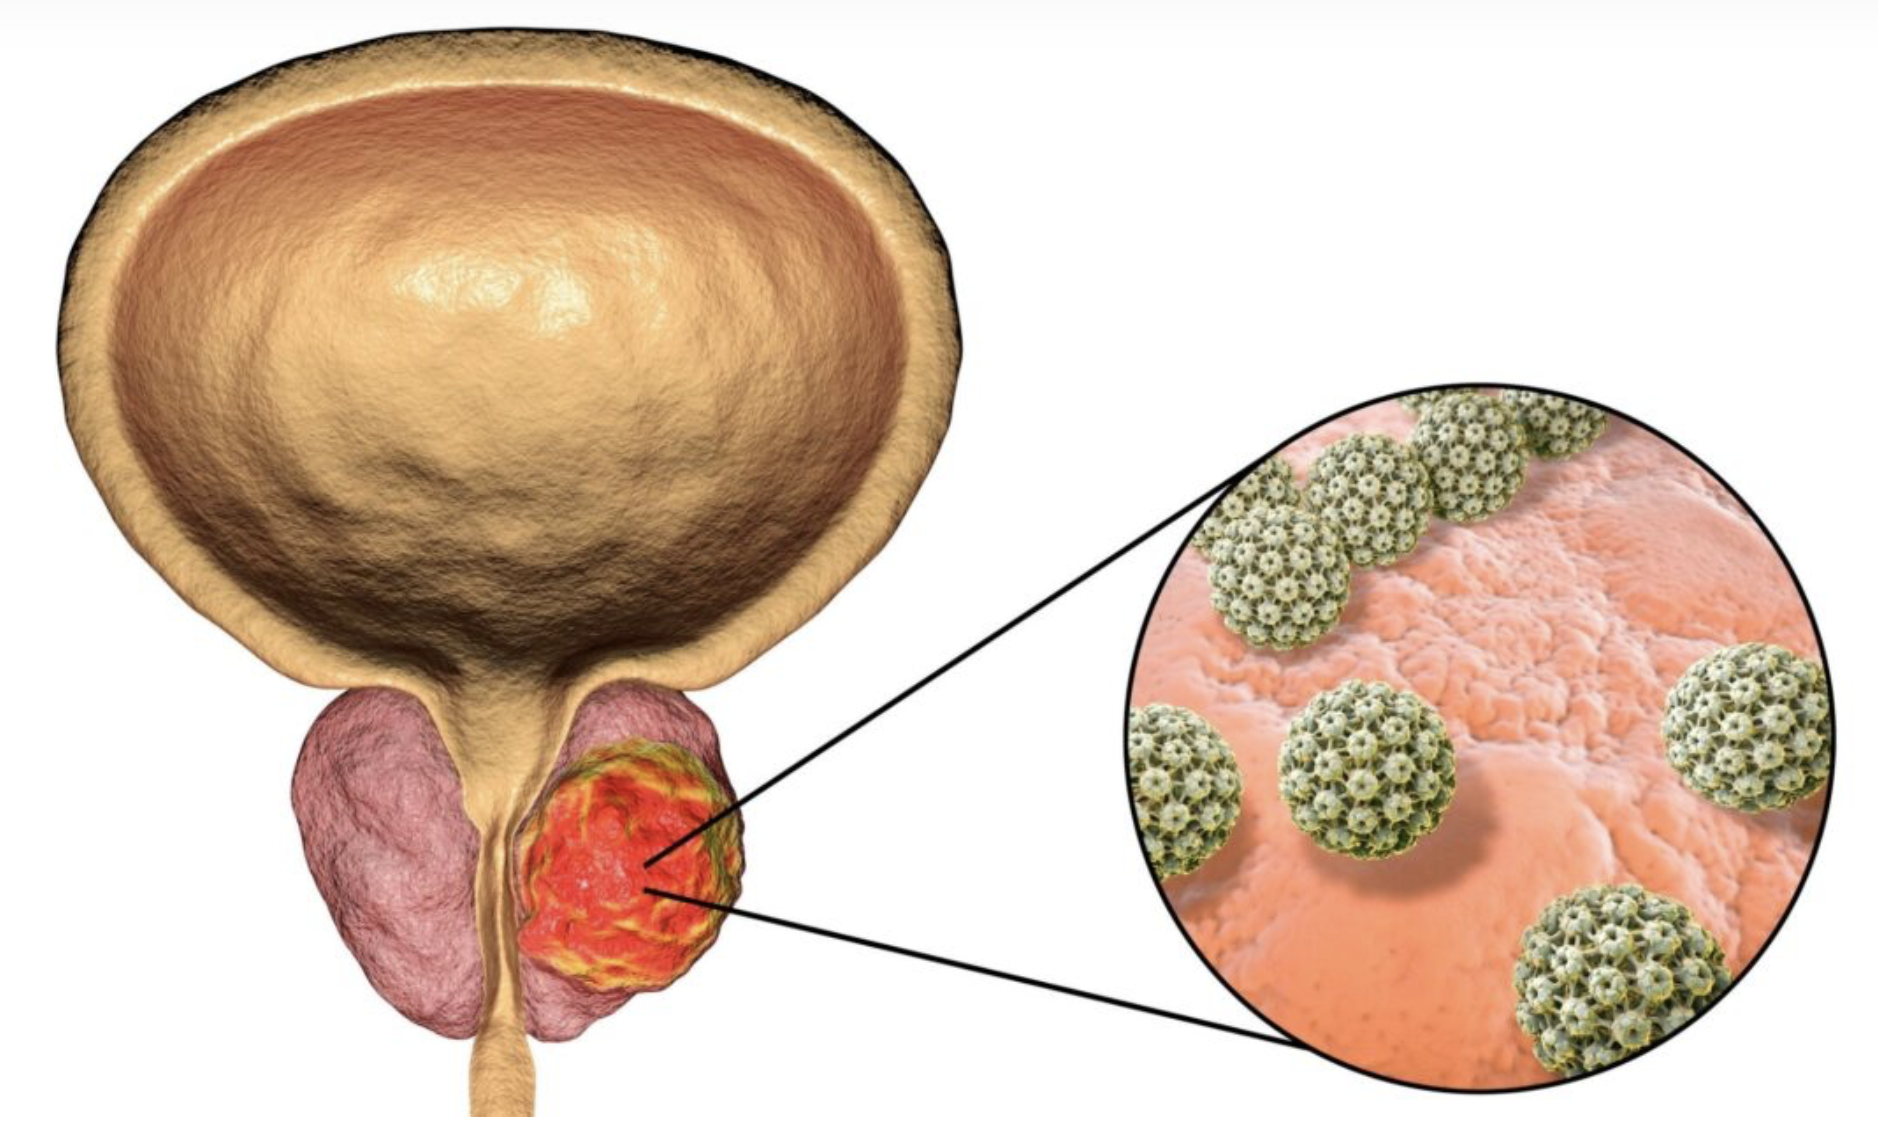

O câncer de próstata é o tumor mais comum entre homens no Brasil, sobretudo após os 50 anos. Em grande parte dos casos evolui de forma silenciosa; quando identificado precocemente, as taxas de cura são altas e os tratamentos costumam ser menos invasivos. A próstata é uma glândula pequena, abaixo da bexiga, responsável por parte do líquido seminal. Quando células prostáticas se multiplicam de forma anormal, pode surgir um tumor que, em situações específicas, pode se espalhar.